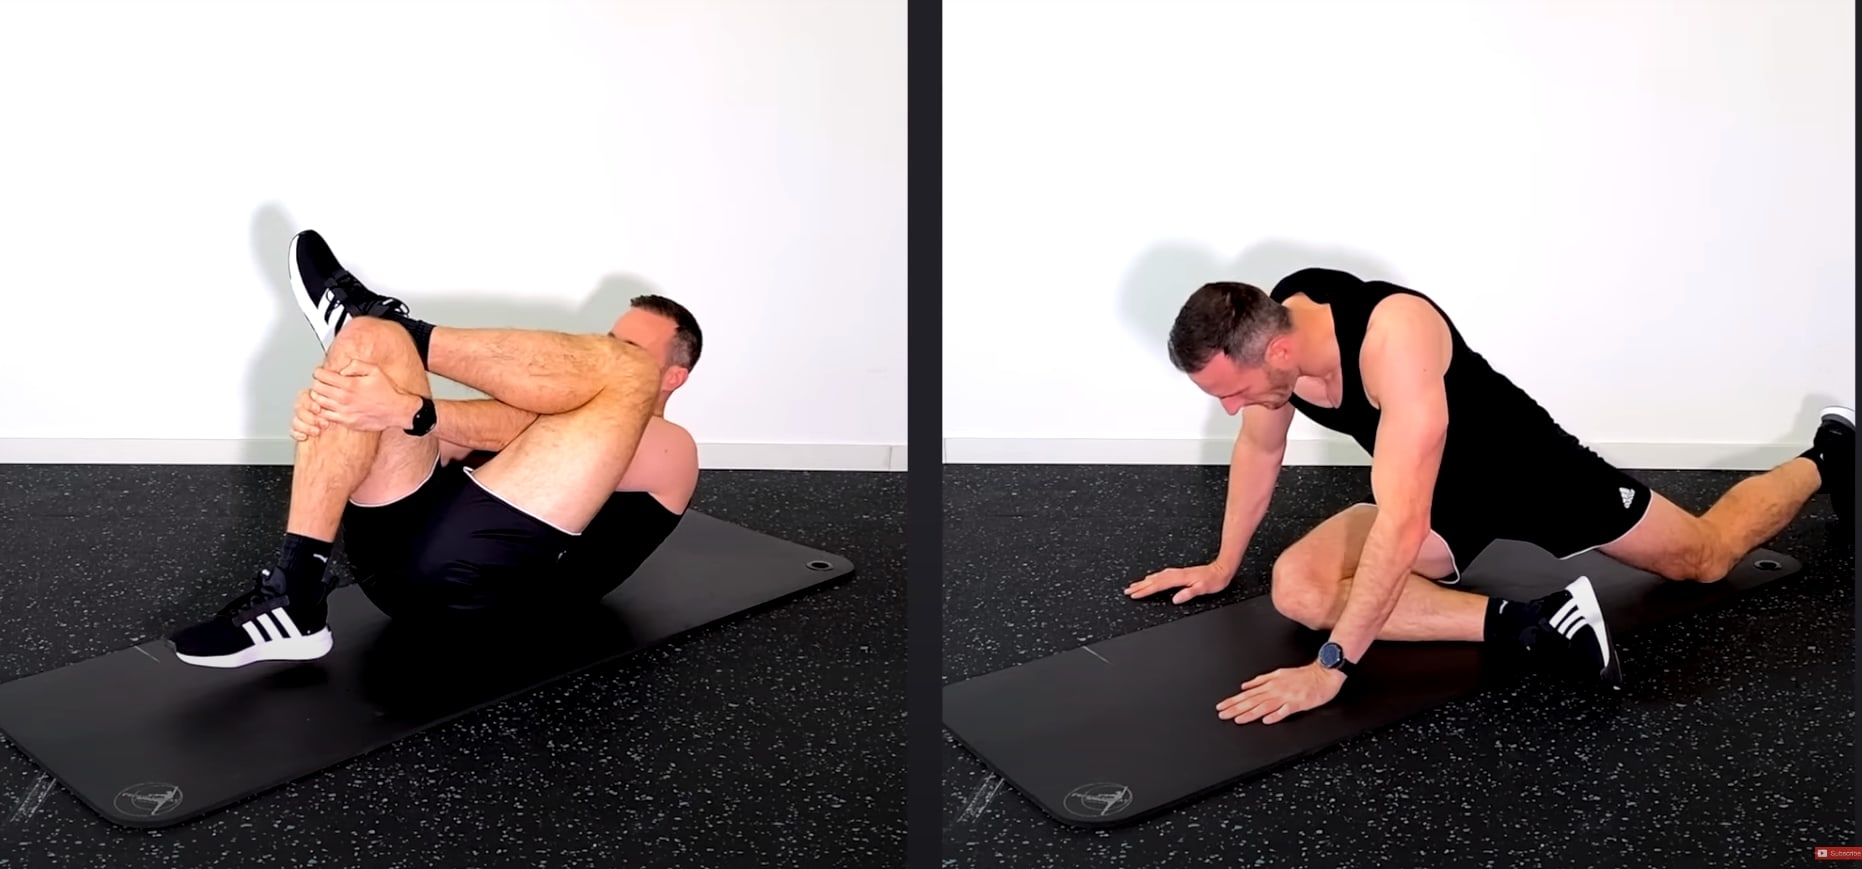

另一个短期方案是拉伸臀部深层肌肉。 这里有两个伸展动作,您不妨在家试试:

- 坐位或仰卧位的标准梨状肌拉伸

- 瑜伽姿势